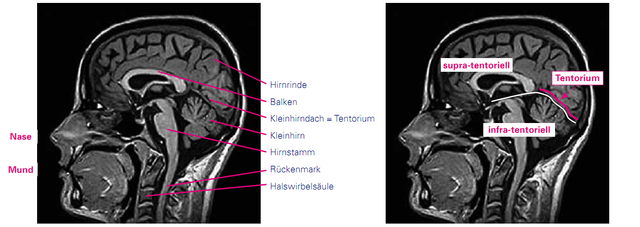

Das Gehirn ist innen und außen von Nervenwasser (Liquor) umgeben. Die „bananenförmigen“ Gebilde in der Mitte des Kernspinbildes (in Queraufnahme (siehe Abbildung)) sind zwei der inneren Nervenwasserräume, auch Ventrikel genannt. Hier werden der erste und zweite Ventrikel symmetrisch in den Hirnhälften sowie vom dritten Ventrikel in der Mitte darunter und dem vierten Ventrikel zwischen Hirnstamm und Kleinhirn (s.u.) unterschieden. Das Kernspin zeigt beim Gehirn Hirnrinde (auch graue Substanz genannt) und Marklager (auch weiße Substanz genannt). In der Hirnrinde befinden sich die Nervenzellkörper, im Marklager die Nervenzellfortsätze. Im Gehirn werden das Großhirn, das Kleinhirn und der Hirnstamm unterschieden. Das Großhirn macht einen Großteil des Gehirns aus und ist für alle Denkprozesse, Wahrnehmungen und Bewegungen zuständig. Die beiden Hirnhälften verbindet der sogenannte Balken. Er liegt oberhalb der beiden seitlichen Nervenwasserräume. Das Kleinhirn ist wesentlich für die Koordination. Es ist durch ein Dach, das „Tentorium“ nach oben vom Großhirn getrennt. In der Beschreibung von MS-Herden wird oft von „supratentoriellen“ und „infratentoriellen“ Herden gesprochen. Damit sind Entzündungsherde ober- bzw. unterhalb einer gedachten Linie auf der Höhe des Kleinhirndachs gemeint. Der Hirnstamm ist die Verbindung von Großhirn und Kleinhirn zum Rückenmark. Hier werden z.B. wichtige Funktionen der Augenbewegungen, das Sprechen und Schlucken sowie weitere unbewusst ablaufende lebenserhaltende Funktionen (Atmung, Temperaturregulation) koordiniert.

Abb.: Kernspin des Kopfes seitlich (T1-Sequenz)